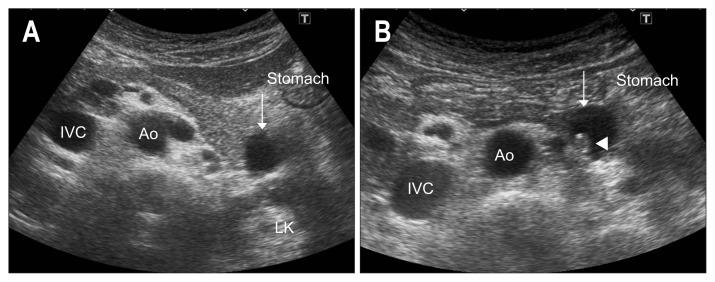

As ultrasound (US) is simple and less invasive than other imaging modalities, this technique is widely used for mass screening. However, visualizing the entire pancreas due to complicated anatomy, obesity and overlying gas can be difficult. US plays a key role in the diagnosis of pancreatic carcinoma (PC), of which tumors smaller than 10 mm (TS1a) and pancreatic carcinoma are expected to have good prognosis. To detect these forms of PC, main pancreatic duct (MPD) dilatation (3 mm or more) and pancreatic cysts (5 mm or larger) are US findings of high-risk individuals (HRIs), and these subjects should be observed periodically. Scanning maneuvers are also important for both screening for PC and follow-up of HRIs. As lesions in the groove area and ventral pancreas do not affect the MPD or extrahepatic bile duct, we should pay attention to these areas. Visualization of the tail is also challenging due to gas and stool in the alimentary tract. As the position of the pancreas changes depending on the body posture, and several different body positions should be employed, such as the right lateral decubitus, sitting, and upright positions, rather than only applying strong compression with the transducer. In cases with poor visualization, the liquid-filled stomach method is highly recommended.

由于超声(US)比其他成像方式简单且侵入性更小,因此该技术被广泛用于大规模筛查。然而,由于胰腺的复杂解剖结构、肥胖和上方气体的影响,很难对整个胰腺进行可视化。US 在胰腺癌(PC)的诊断中起着关键作用,其中直径小于 10mm(TS1a)和胰腺神经内分泌肿瘤的肿瘤预计具有良好的预后。为了检测这些形式的 PC,主胰管(MPD)扩张(3mm 或更大)和胰腺囊肿(5mm 或更大)是高危人群(HRIs)的 US 发现,这些患者应定期观察。扫描手法对于 PC 的筛查和 HRIs 的随访也很重要。由于沟区和胰头区域的病变不会影响胰管或肝外胆管,因此我们应该注意这些区域。由于消化道中的气体和粪便,尾部的可视化也具有挑战性。由于胰腺的位置随体位变化而变化,因此应采用几种不同的体位,如右侧卧位、坐位和立位,而不是仅用探头进行强力压迫。在可视化效果不佳的情况下,强烈推荐使用充满液体的胃法。